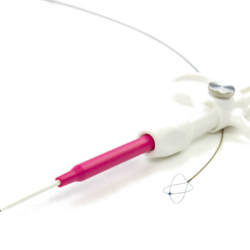

RocaJJ Soft – PolyUrethane Double Loop Ureteral Stents

Stiff Kit – With Nitinol Guide Wire